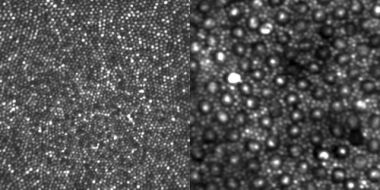

As a result the device has been able to achieve an imaging resolution of nearly two microns, which is roughly the diameter of a single rod cell in the human eye.

Retinas contain both rod and cone cells, and although rods provide monochromatic images and contribute directly only to night vision, their health turns out to act as an early warning for a number of retinal diseases. Hence the interest in accurately imaging individual cells from organizations such as Research to Prevent Blindness, which funds research aimed at preventing a range of vision disorders.

"Ophthalmic adaptive optics has been used for over ten years, but until recently could only visualize cone photoreceptors in the central ten degrees of the retina," said Alf Dubra of MCW. "We can now resolve the smallest cones in the retina, which are at the foveal center and provide the highest spatial resolution to our visual system. More importantly from the clinical point of view, we can also now see the rod photoreceptor mosaic in a large number of subjects."

MCW is planning further improvements to the wavefront correctors and adaptive optics control algorithms, while continuing to work on making its instruments suitable for clinical environments. But the most important challenge has now become image processing and interpretation. Although images showing the retinal cell mosaics in vivo have enormous potential to impact the diagnosing and care of retinal disease, researchers are as yet not certain precisely which key metrics should be derived from the pictures. MCW and others are exploring the more obvious numbers to extract, such as cell density, but variability across individuals might be very large.